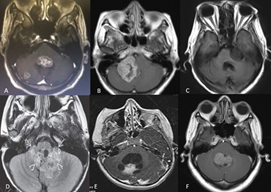

The tumor lesions of the PF are very varied, and their frequency of diagnosis has a marked pattern in relation to age and the affected anatomical structure (Figure 2). Metastases are the most frequent tumors in adults, representing approximately 30% of lesions. Around 50% of these metastases are of pulmonary origin, followed by breast, gastrointestinal, urogenital tumors and melanomas.1 Among primary tumors, meningiomas are the most common in adults.1 In children and adolescents, the frequency is determined by the location of the tumor lesion. Globally, glial tumors are the most prevalent.1 In the case of vermian lesions,1,3,25,29 medulloblastoma is common. Metastases are very rare in people under 20 years of age.1,30 Table 1 summarizes the different PF tumors according to anatomical location.

Figure 2 PF tumors. Diagnostic imaging registry courtesy Hospital Universitario del Caribe (Cartagena). (A) lung tumor metastasis in the fourth ventricle and right cerebellar hemisphere; (B) right APC meningioma; (C) left APC squamous cell tumor; (D) ependymoma; (E) right cerebellar hemisphere pilocytic astrocytoma; (F) medulloblastoma. APC, cerebellopontine angle.